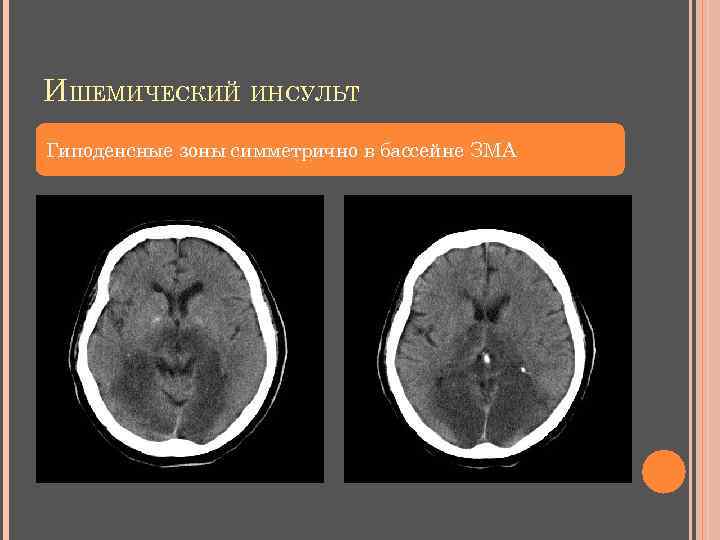

ИШЕМИЧЕСКИЙ ИНСУЛЬТ I стадия – 0 -2 суток (фокальный цитотоксический отек мозга) Симптом повышения плотности артерий Утрата визуализации островка Исчезновение очертаний лентикулярного ядра Утрата дифференцировки белого и серого вещества Сглаженность корковых извилин КТ - негативны – лакунарные инфаркты, инфаркты ствола и мозжечка

ИШЕМИЧЕСКИЙ ИНСУЛЬТ II стадия – до 8 суток (нарастающий цитотоксический и вазогенный отек ГМ, распад зоны некроза) снижение плотности в зоне инфаркта нарастает «масс-эффект» признаки геморрагического пропитывания – участки повышения плотности в подкорковых узлах и по ходу извилин (4 -6 сутки)

ИШЕМИЧЕСКИЙ ИНСУЛЬТ III стадия – 9 -21 сутки (организация инфаркта: резорбция и репарация в зоне некроза мозговой ткани, уменьшение отека) изоденсная фаза (эффект затуманивания) – 9 -14 сутки гиподенсная зона – 15 -21 день регресс «масс-эффекта» IV стадия – свыше 1 мес. (формирование зоны энцефаломаляции (постинфарктной кисты), окруженной глиозно измененным мозговым веществом) гиподенсная зона (псевдокиста) заместительная гидроцефалия

ИШЕМИЧЕСКИЙ ИНСУЛЬТ Гиподенсные зоны симметрично в бассейне ЗМА